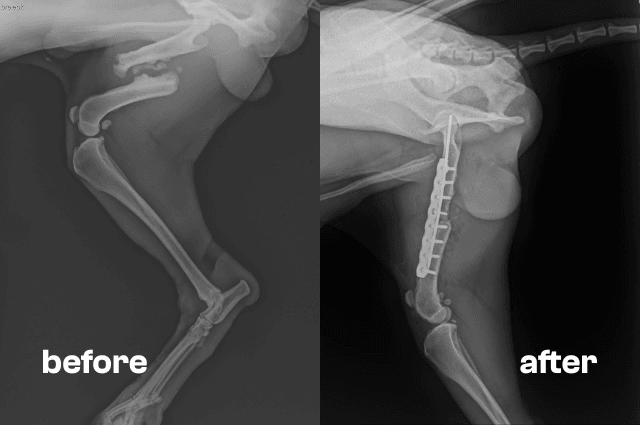

Veterinary examination confirmed a severe fracture of the femur. Immediate surgery was necessary, which fortunately went smoothly. The dog is now still in the care of the clinic, awaiting removal of the stitches and a follow-up x-ray to verify that the bone is healing properly.